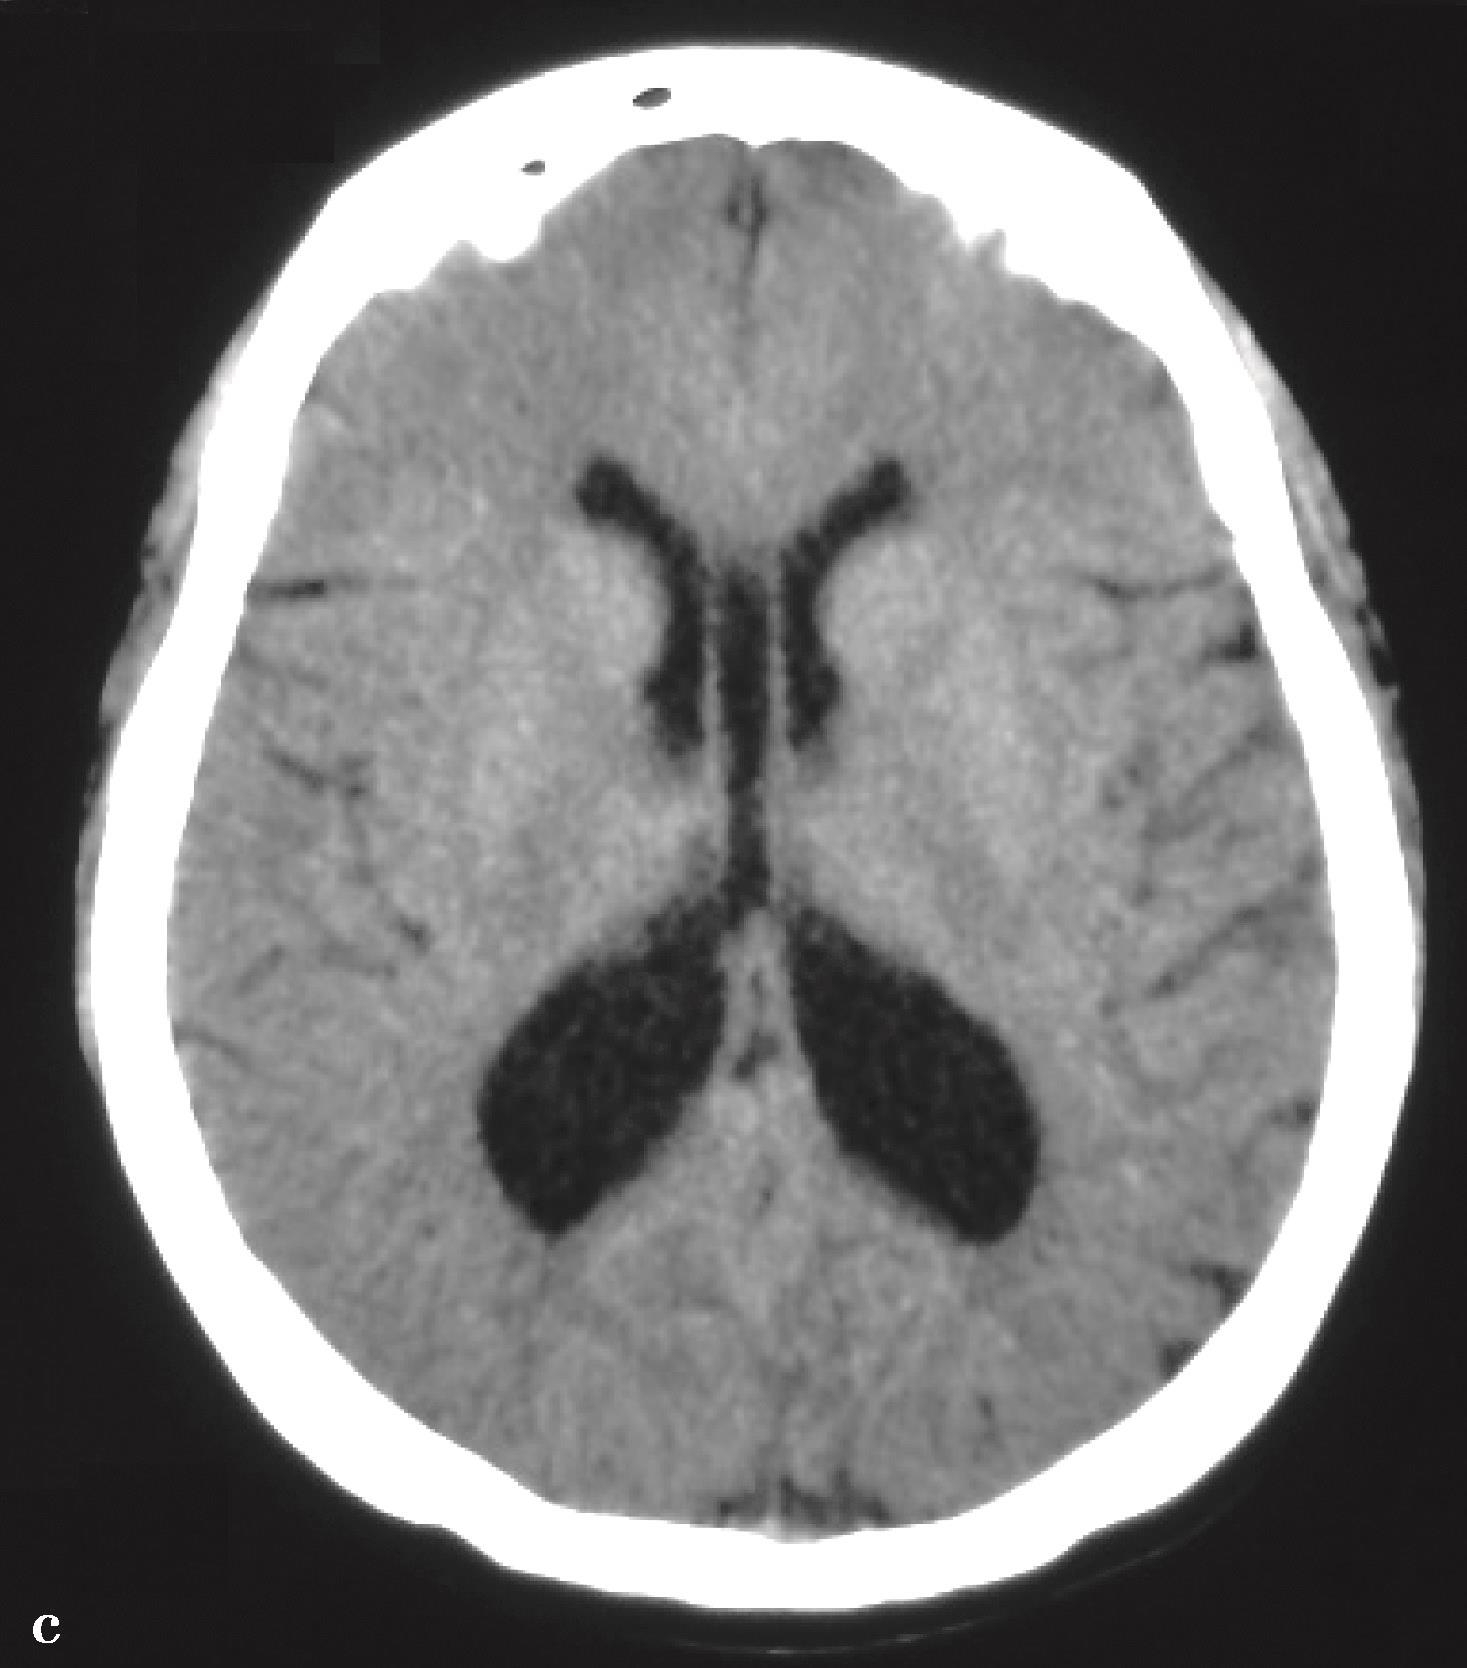

图3-1-2-5 导水管支架植入